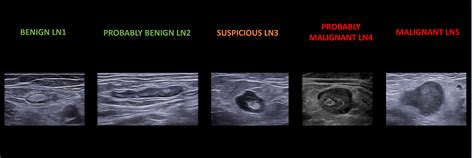

• Size and Shape: Normal nodes are typically oval, whereas malignant nodes may appear more rounded or spherical.

• Internal Architecture: Healthy nodes have a clear, bright central area called the “fatty hilum.” The absence of this hilum can be a warning sign.

• Blood Flow Patterns: Using Doppler technology, radiologists can assess how blood flows into the node. Abnormal vascularity is often a key marker for pathology.

• Border Definition: Clear, regular borders are generally reassuring, while irregular or “matted” borders may warrant biopsy.

Feature Benign (Normal) Appearance Potentially Malignant Appearance

Shape Oval (Kidney-shaped) Round

Hilum Visible, bright, central Absent or displaced

Borders Smooth and distinct Irregular or indistinct

Internal Echo Homogeneous Heterogeneous (Mixed)